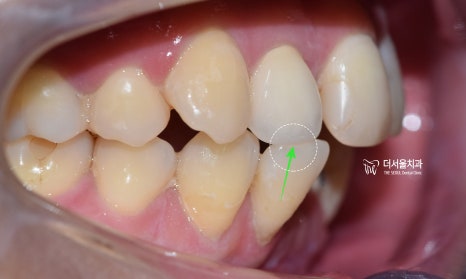

측절치의 경우에는 윗니가 아랫니가

덮고 있어야 되는데 절단연 끼리

맞닿고 있는 egde bite 교합의

양상을 보여주고 있습니다.

현 상황을 지속적으로 둘 시에는,

교합 관계와 치열이 금새 무너집니다.

3. 인비절라인 교정 시작

저는 인비절라인 으로 교정치료를

하는 것을 좋아합니다.

환자들도 상당히 좋아합니다.

이미 어느정도 치아의 움직임이

일어난 상태로 사진을 찍었으며

치아의 바깥면에 붙어있는 뽀죡뾰족한

어태치먼트들이 인비절라인 장치와

만나서 치아를 이동시킵니다.

은색 버튼은, 더 정밀하게 치아를

이동 시키는데 도움을 주는

부가 장치입니다.